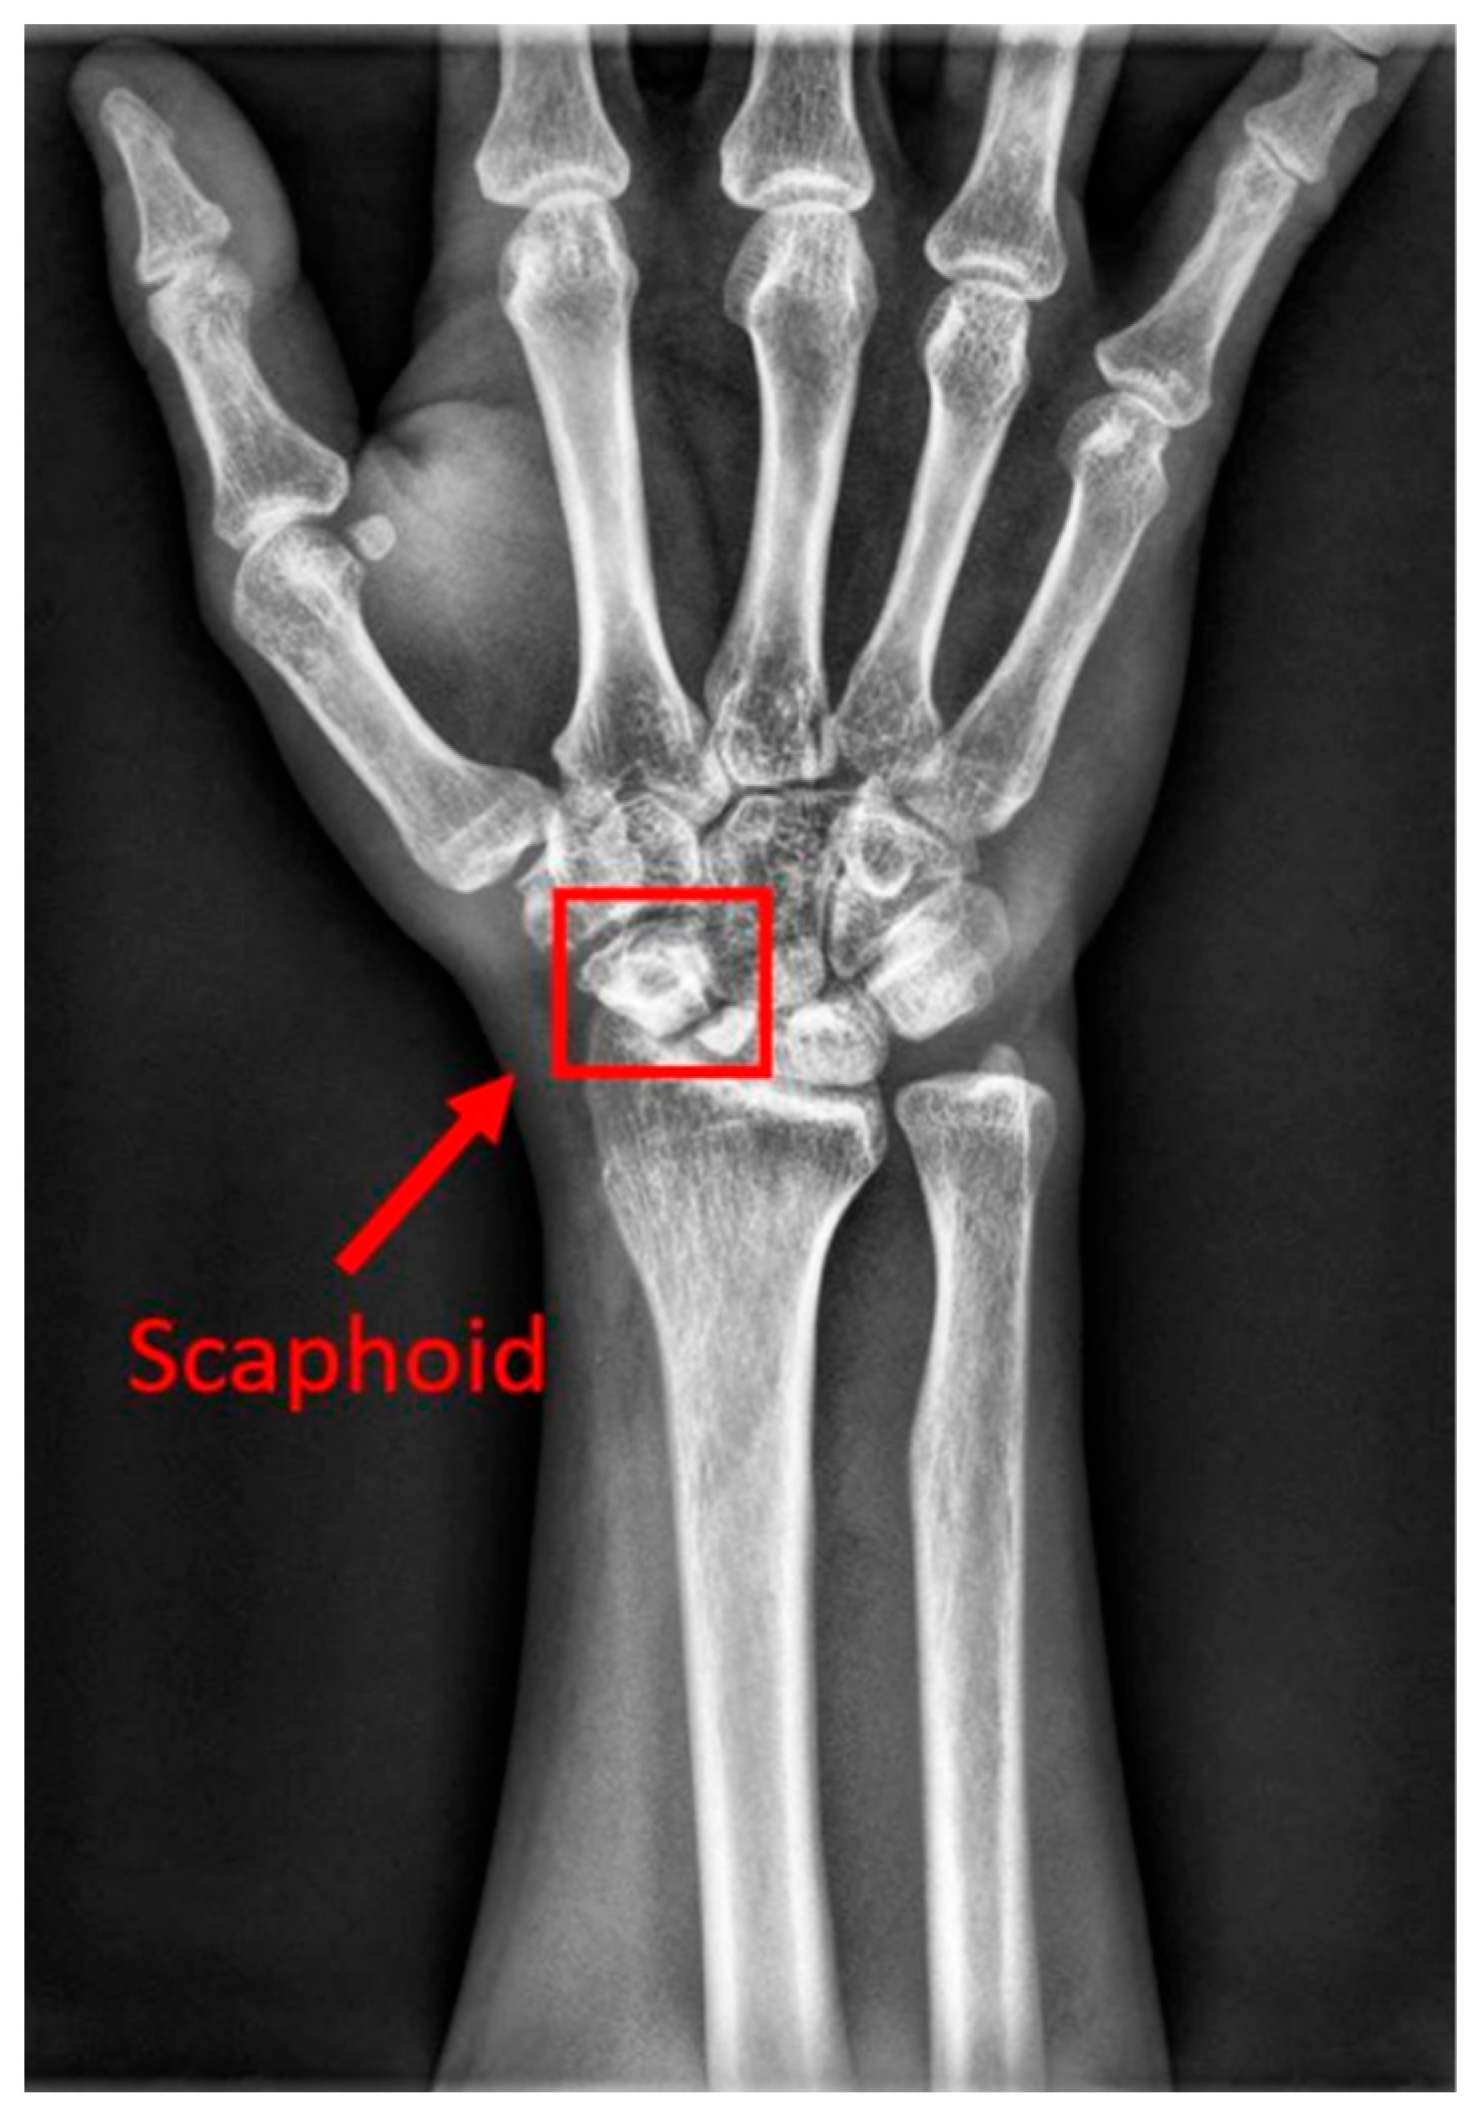

The human wrist consists of eight carpal bones, with the scaphoid bone being the largest. Located under the thumb and near the arm, as indicated by the red box in Figure 1, the scaphoid is prone to injury because of its location. It can fracture not only from severe accidents but also from falls where one braces themselves with the wrist or during athletic activities. A scaphoid fracture may not always cause severe pain; symptoms can be mild, leading individuals to believe they have merely sprained their wrist and that it will heal without medical intervention. Scaphoid fractures account for 2% to 7% of all fractures and 60–70% of carpal bone fractures. General treatment often involves screw fixation surgery because of its short operation time and good recovery outcomes. However, accurate localization of both the scaphoid and the fracture site is essential for implanting the screw at the optimal angle. Physicians typically use X-rays for diagnosis, but since X-rays are two-dimensional projections of a three-dimensional object, the scaphoid bone may overlap and not be fully visible in the two-dimensional image. This is particularly problematic for non-displaced fractures, which can be challenging to detect with the naked eye and are termed occult fractures, as shown in Figure 2.

Figure 1.

The location of the scaphoid bone. The scaphoid bone is within the red box.